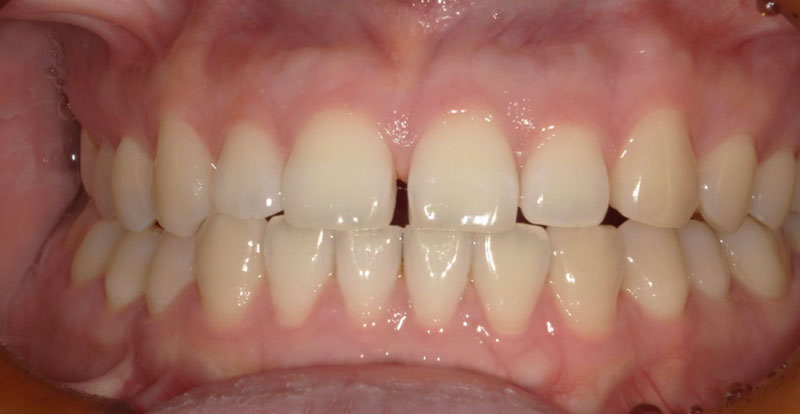

患者さんの悩みは下の前歯が出ていること、いわゆる受け口が気になるとのことでした。

非抜歯矯正を望まれたので非抜歯矯正の得意なマウスピース矯正のインビザラインをご提案いたしました。

患者さんの悩みであった前歯の見た目が改善されたこと、しっかり奥歯で噛めることでとても喜ばれていました。

| 主訴 | 下の前歯が出ているのが気になる |

| 所見 | 反対咬合 |

| 治療装置 | インビザライン |

| 装置装着部位 | 全顎 |

| 治療費 | 88万円(税込) |

| 治療期間 | 約2年(約30回通院) |